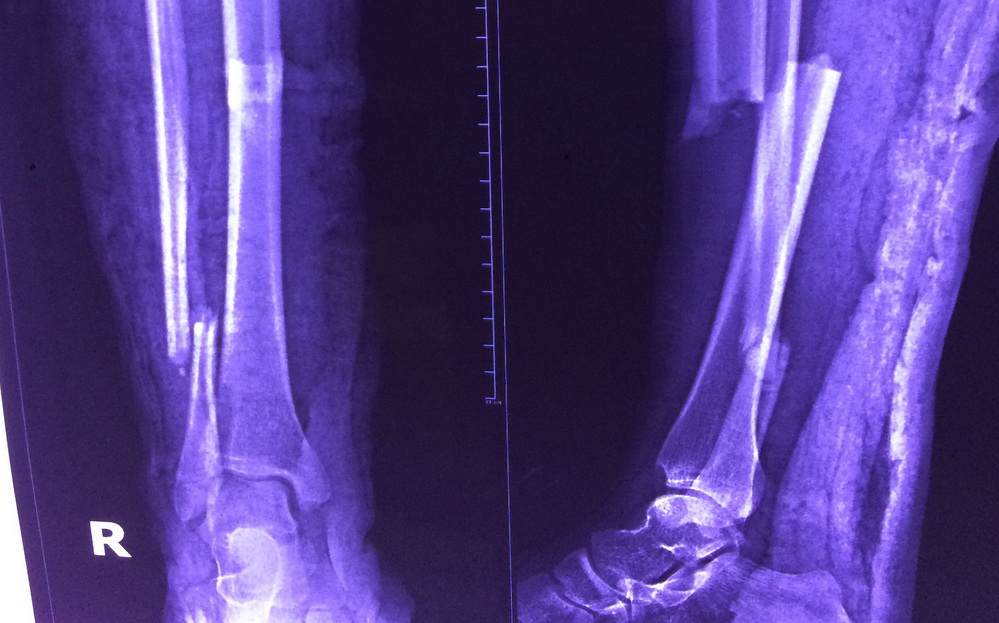

Hình ảnh xquang kiểm tra chân của chi D. bị gãy phức tạp - Ảnh: Bệnh viện cung cấp

Các bác sĩ ghi nhận bệnh nhân bị gãy xương cẳng chân bên phải (đoạn ống quyển) thành 2 đoạn phức tạp, ca mổ nguy hiểm vì chỉ cần đi một bước lên cầu thang bệnh nhân đã khó thở, tím tái.

Sau một giờ phẫu thuật kết hợp xương bằng đinh nội tủy có chốt, ca mổ thành công tốt đẹp.